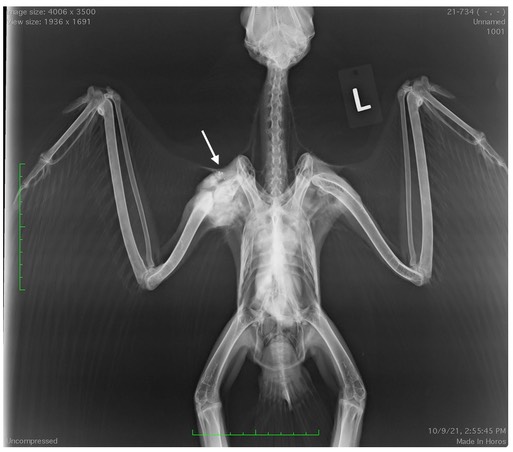

Gunshot Red-tailed Hawks 21-730 and 21-734

Below are examples of the usefulness of whole-body radiographs. The first radiograph shows an air rifle pellet near the left wrist and partially healed fractures of the left ulna and metacarpals. Notice the difference in muscle mass between the birds left and right side. The muscle on the left side is atrophied compared to the muscle on the right side because the bird was unable to use his left wing after being shot.